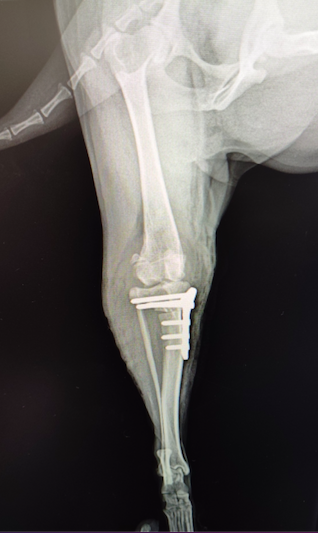

犬の前十字靭帯断裂(TPLO法)

トイプードル 4歳 避妊メス

【レントゲン検査】

・右膝関節内の関節液貯留所見、脛骨前方偏位像確認

TPLO法を実施